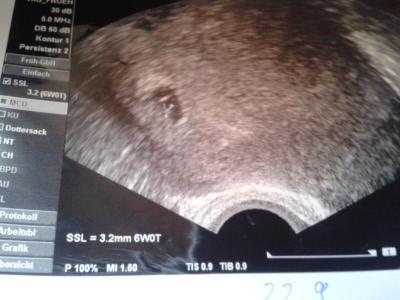

Hallo zusammen hatte heute mein zweiten Fa Termin slles ist supper Herz schlug fleißig. Bin in der 7 Woche Hoffe es bleibt bei mir

Bild zu Mein Arzt Termin war erfolgreich - Schwanger - wer noch? Rund um die Schwangerschaft